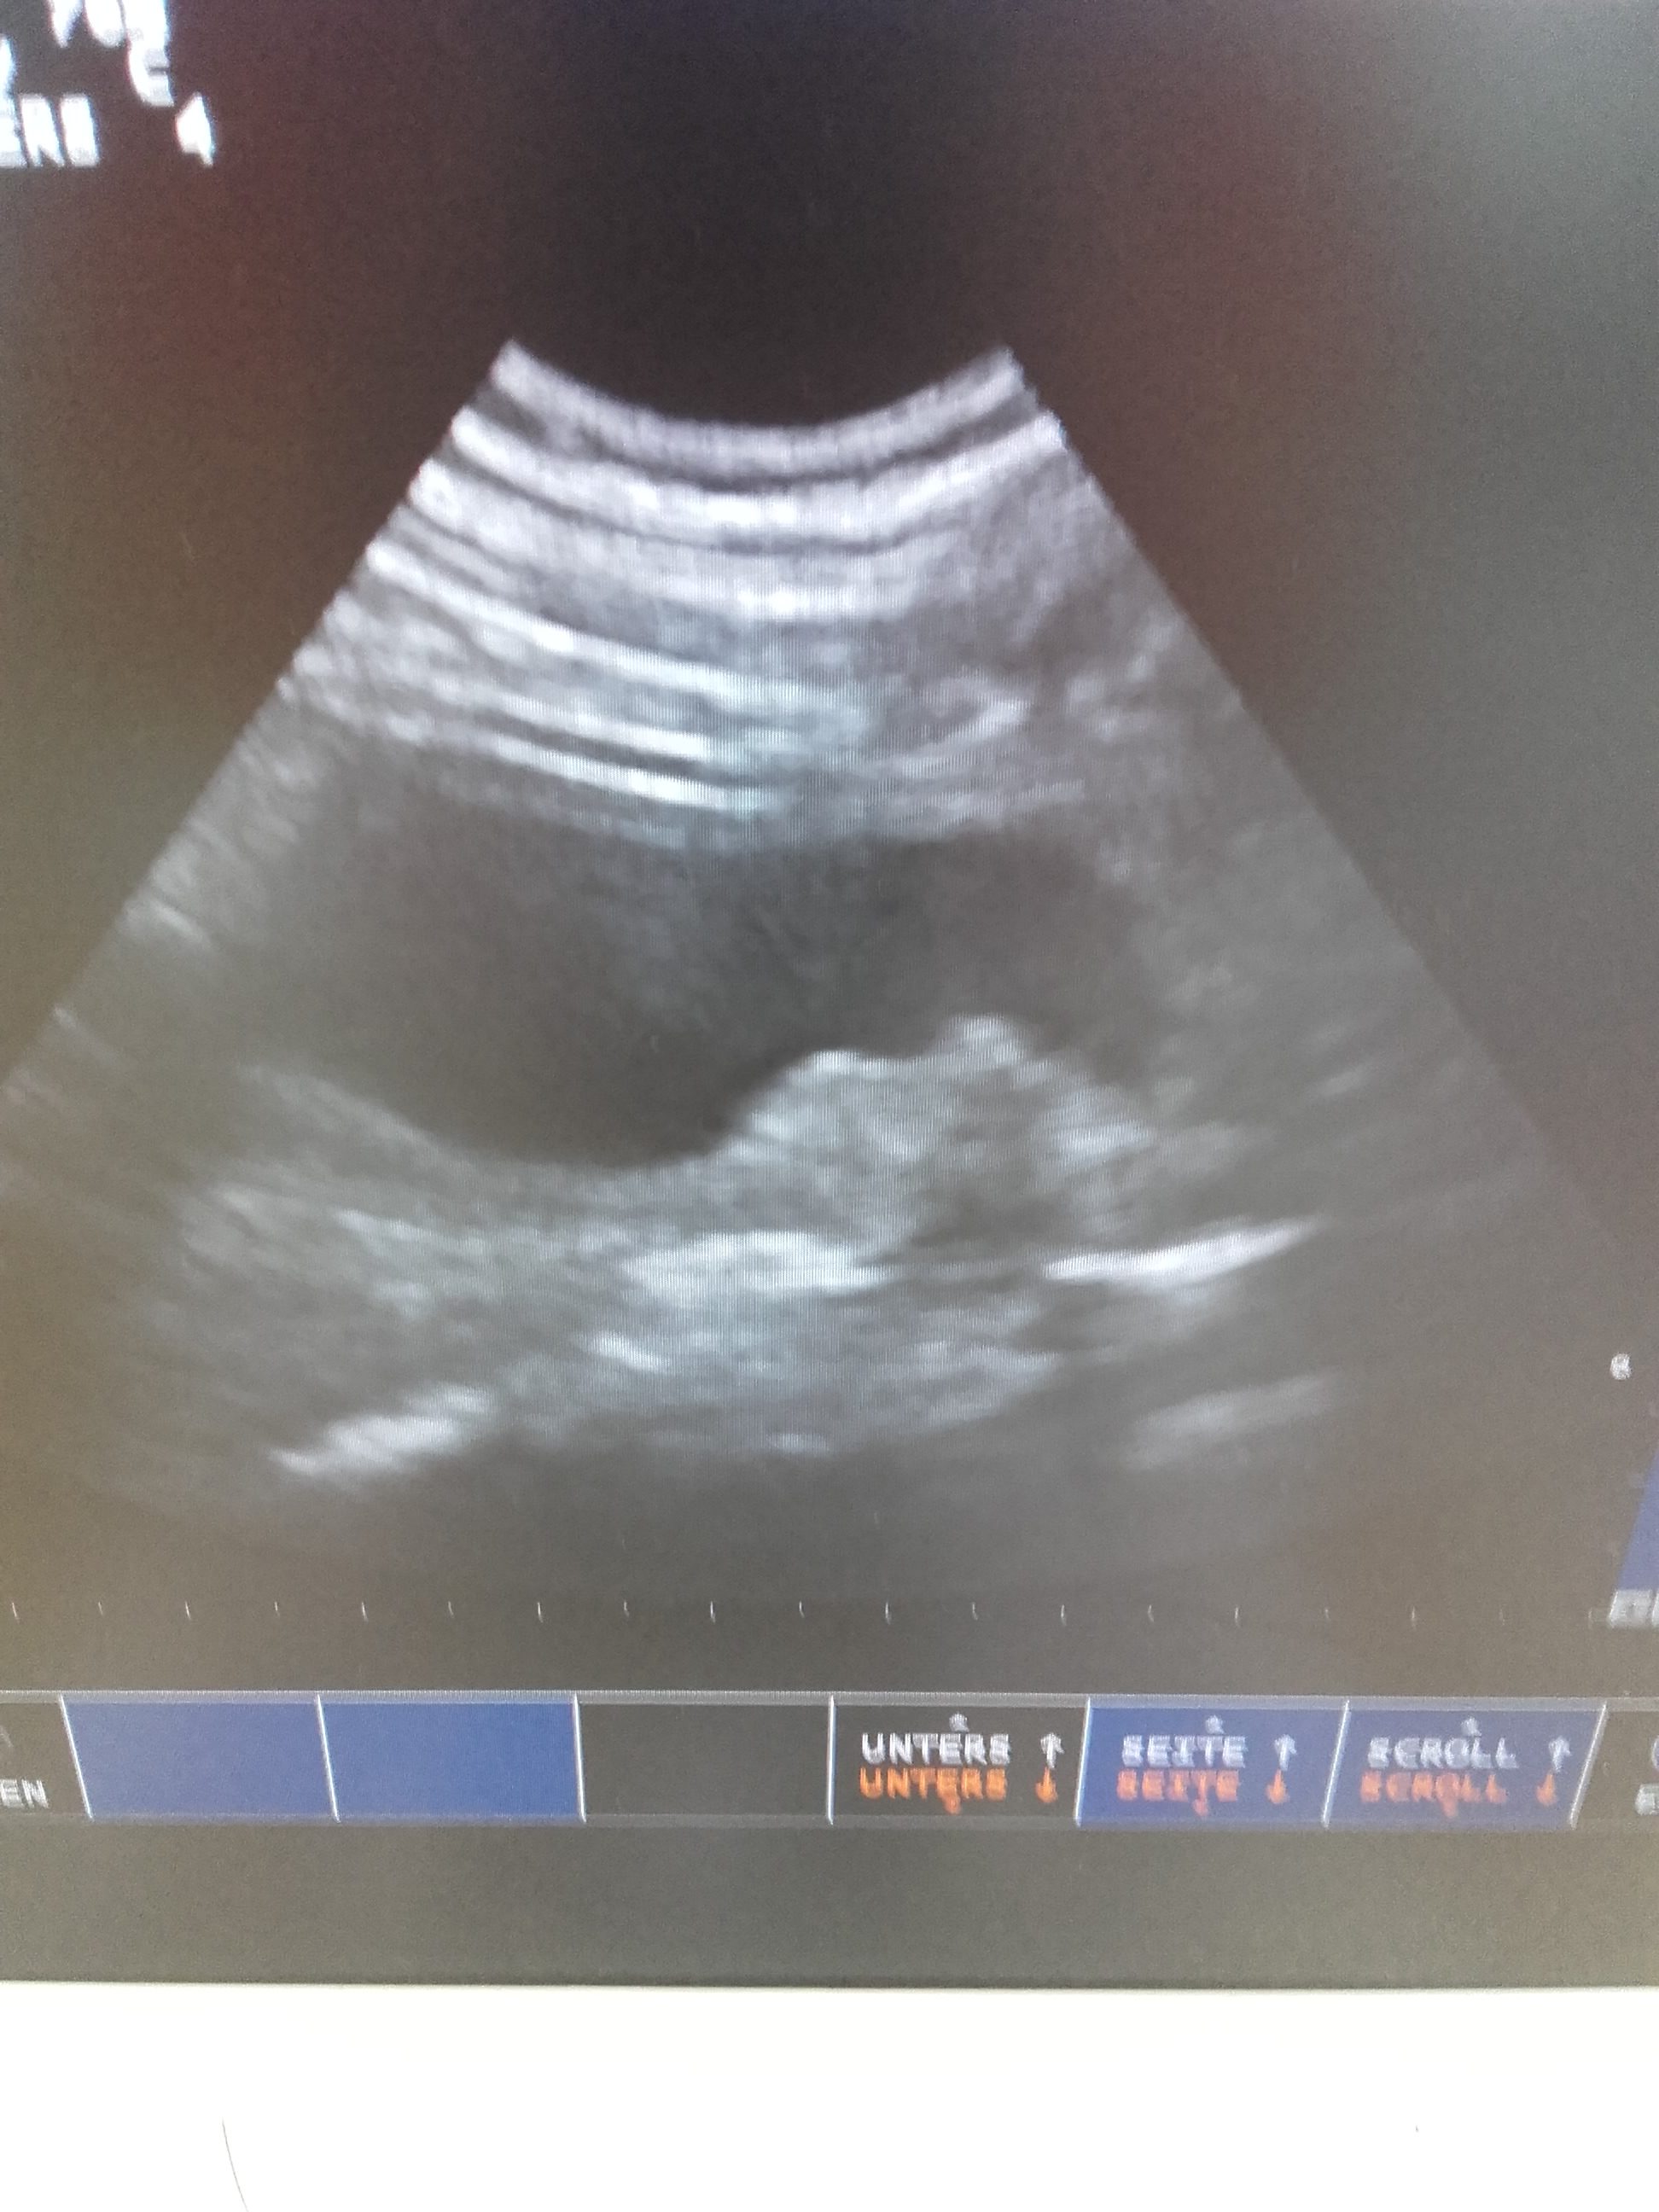

- Ultraschall der Blase.